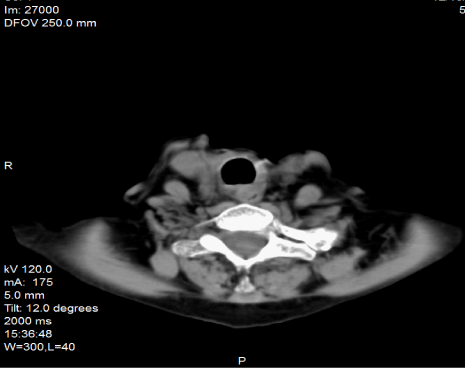

Combined histological and immune histological analyses led to the diagnosis of la diffuse large B-cell lymphoma of the follicular centre/ activated like-cell-non GCC, with a high proliferation index (Mib1/Ki-67 : 90%) , positive LCA(CD45Rb), CD10, CD75, CD79a, BSAP, BCL6, BCL2, MUM1, k-light chain, p53 and p63 and negative reaction of the neoplastic cells for CKAE1-3, EMA, HBME1,Thyreogloboulin, Galectin-3 and others (Figure 2).4

Figure 2e H/E stain.